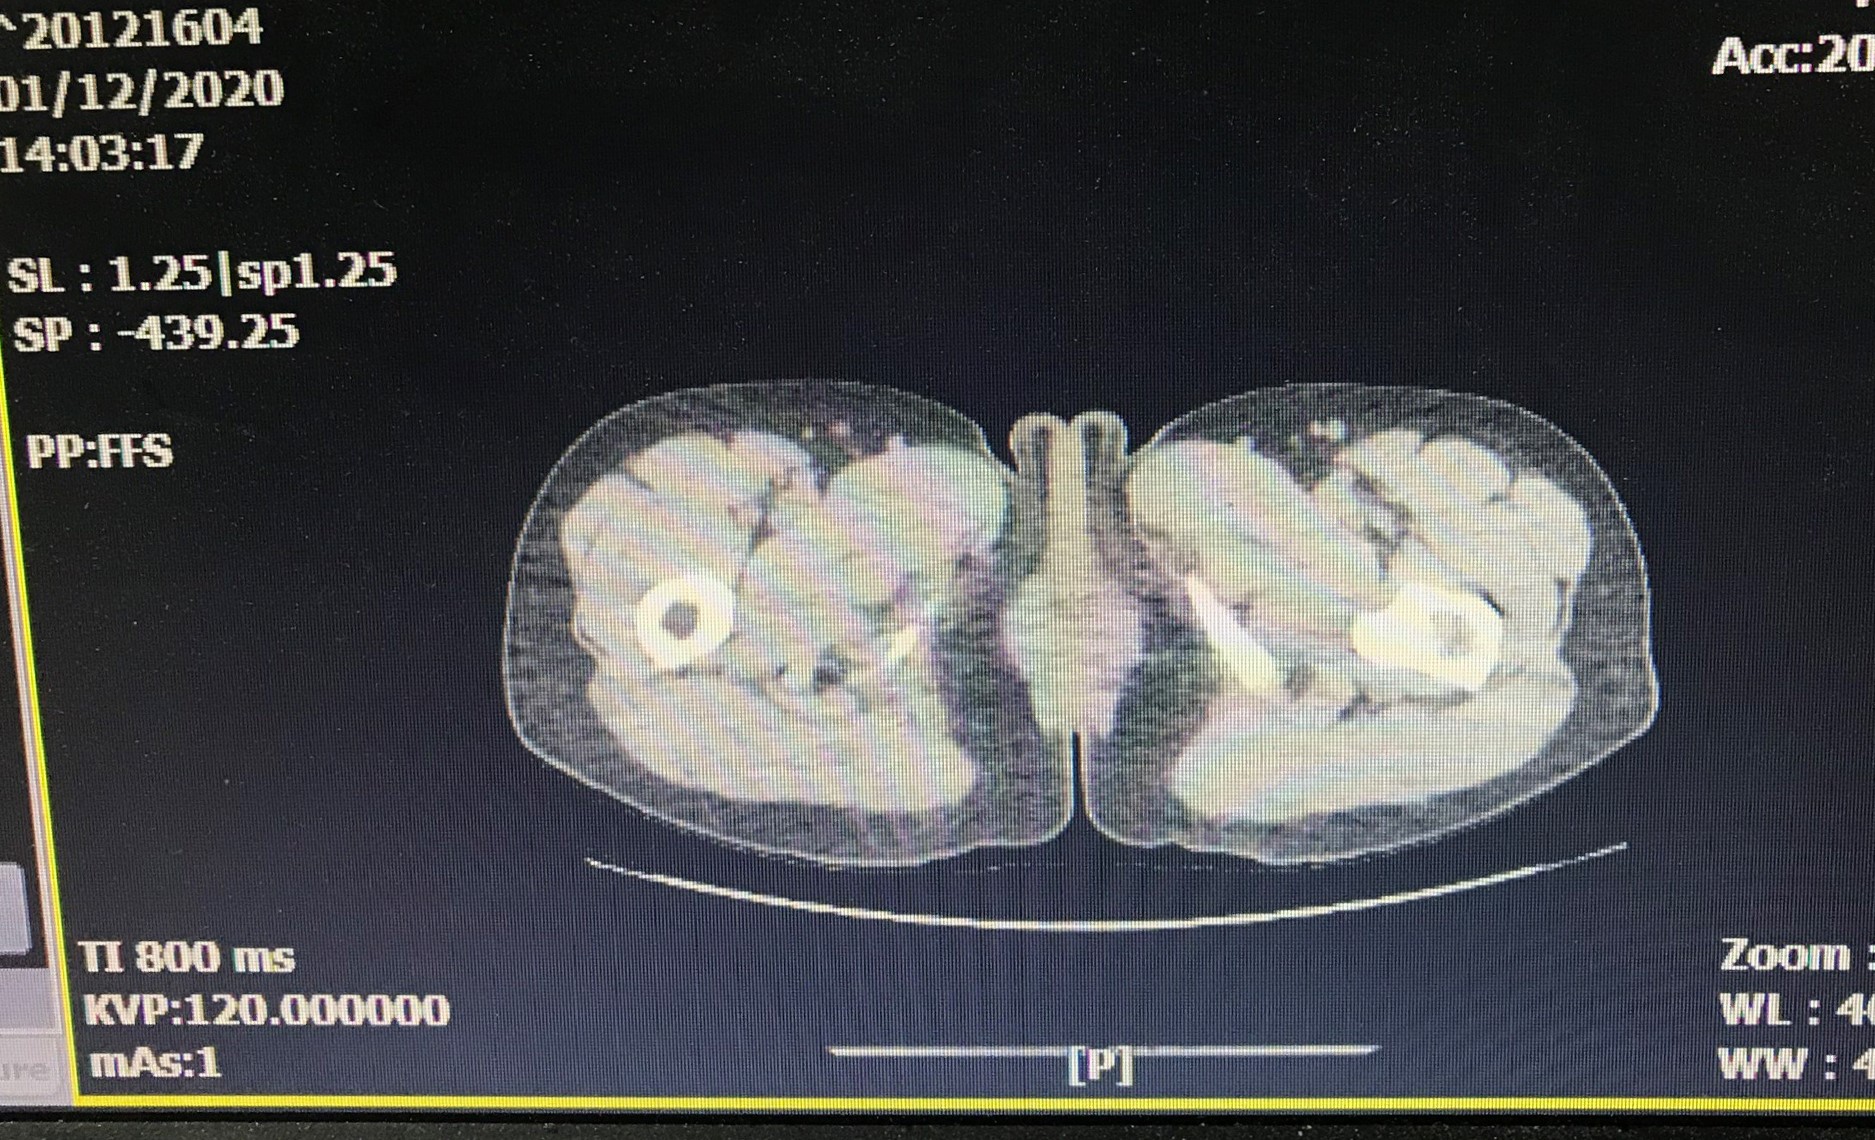

Bệnh nhân P.T.T, 50 tuổi, ở Tiên Lãng, Hải Phòng đau tức vùng thắt lưng 1 năm nay. Qua thăm khám và hình ảnh chụp Xquang, các bác sĩ tại Bệnh viện đa khoa Quốc tế Hải Phòng chẩn đoán người bệnh có sỏi san hô, kích thước 3cm và nhiều sỏi rải rác trong thận phải.

Quá trình thực hiện, các bác sĩ đã tiến hành rạch da khoảng 0,5cm vùng thắt lưng, tạo một đường hầm nhỏ từ ngoài da vào thận, đưa máy nội soi qua đường hầm tìm sỏi. Sau đó sử dụng tia Laser tán vỡ sỏi thành từng mảnh nhỏ và hút các mảnh sỏi vỡ này ra ngoài qua đường hầm. Kết quả kiểm tra sau mổ, sỏi đã được tán hết, trong thận không còn sỏi và bệnh nhân được hẹn tái khám sau 1 tháng.